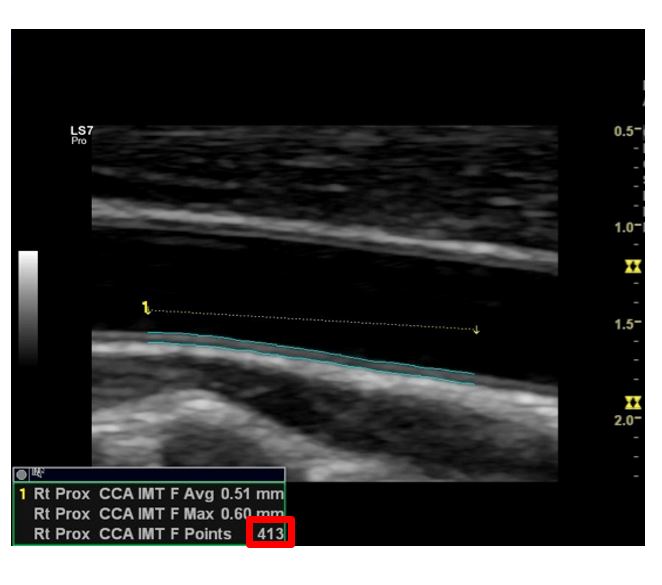

Auto IMT

경동맥 검사시 동맥경화나 심혈관계 평가를 위해 내막-중막 두께(Intima Media Thickness, IMT)를 자동 측정하는 기술입니다.

범위를 선택할 때 수백 곳의 포인트에서 내막-중막의 두께를 측정하여 평균치를 보여줍니다.

넓은 범위에 걸쳐서 자동 측정해주기 때문에 측정자에 관계없이 신뢰도 있는 데이터를 확인할 수 있습니다.